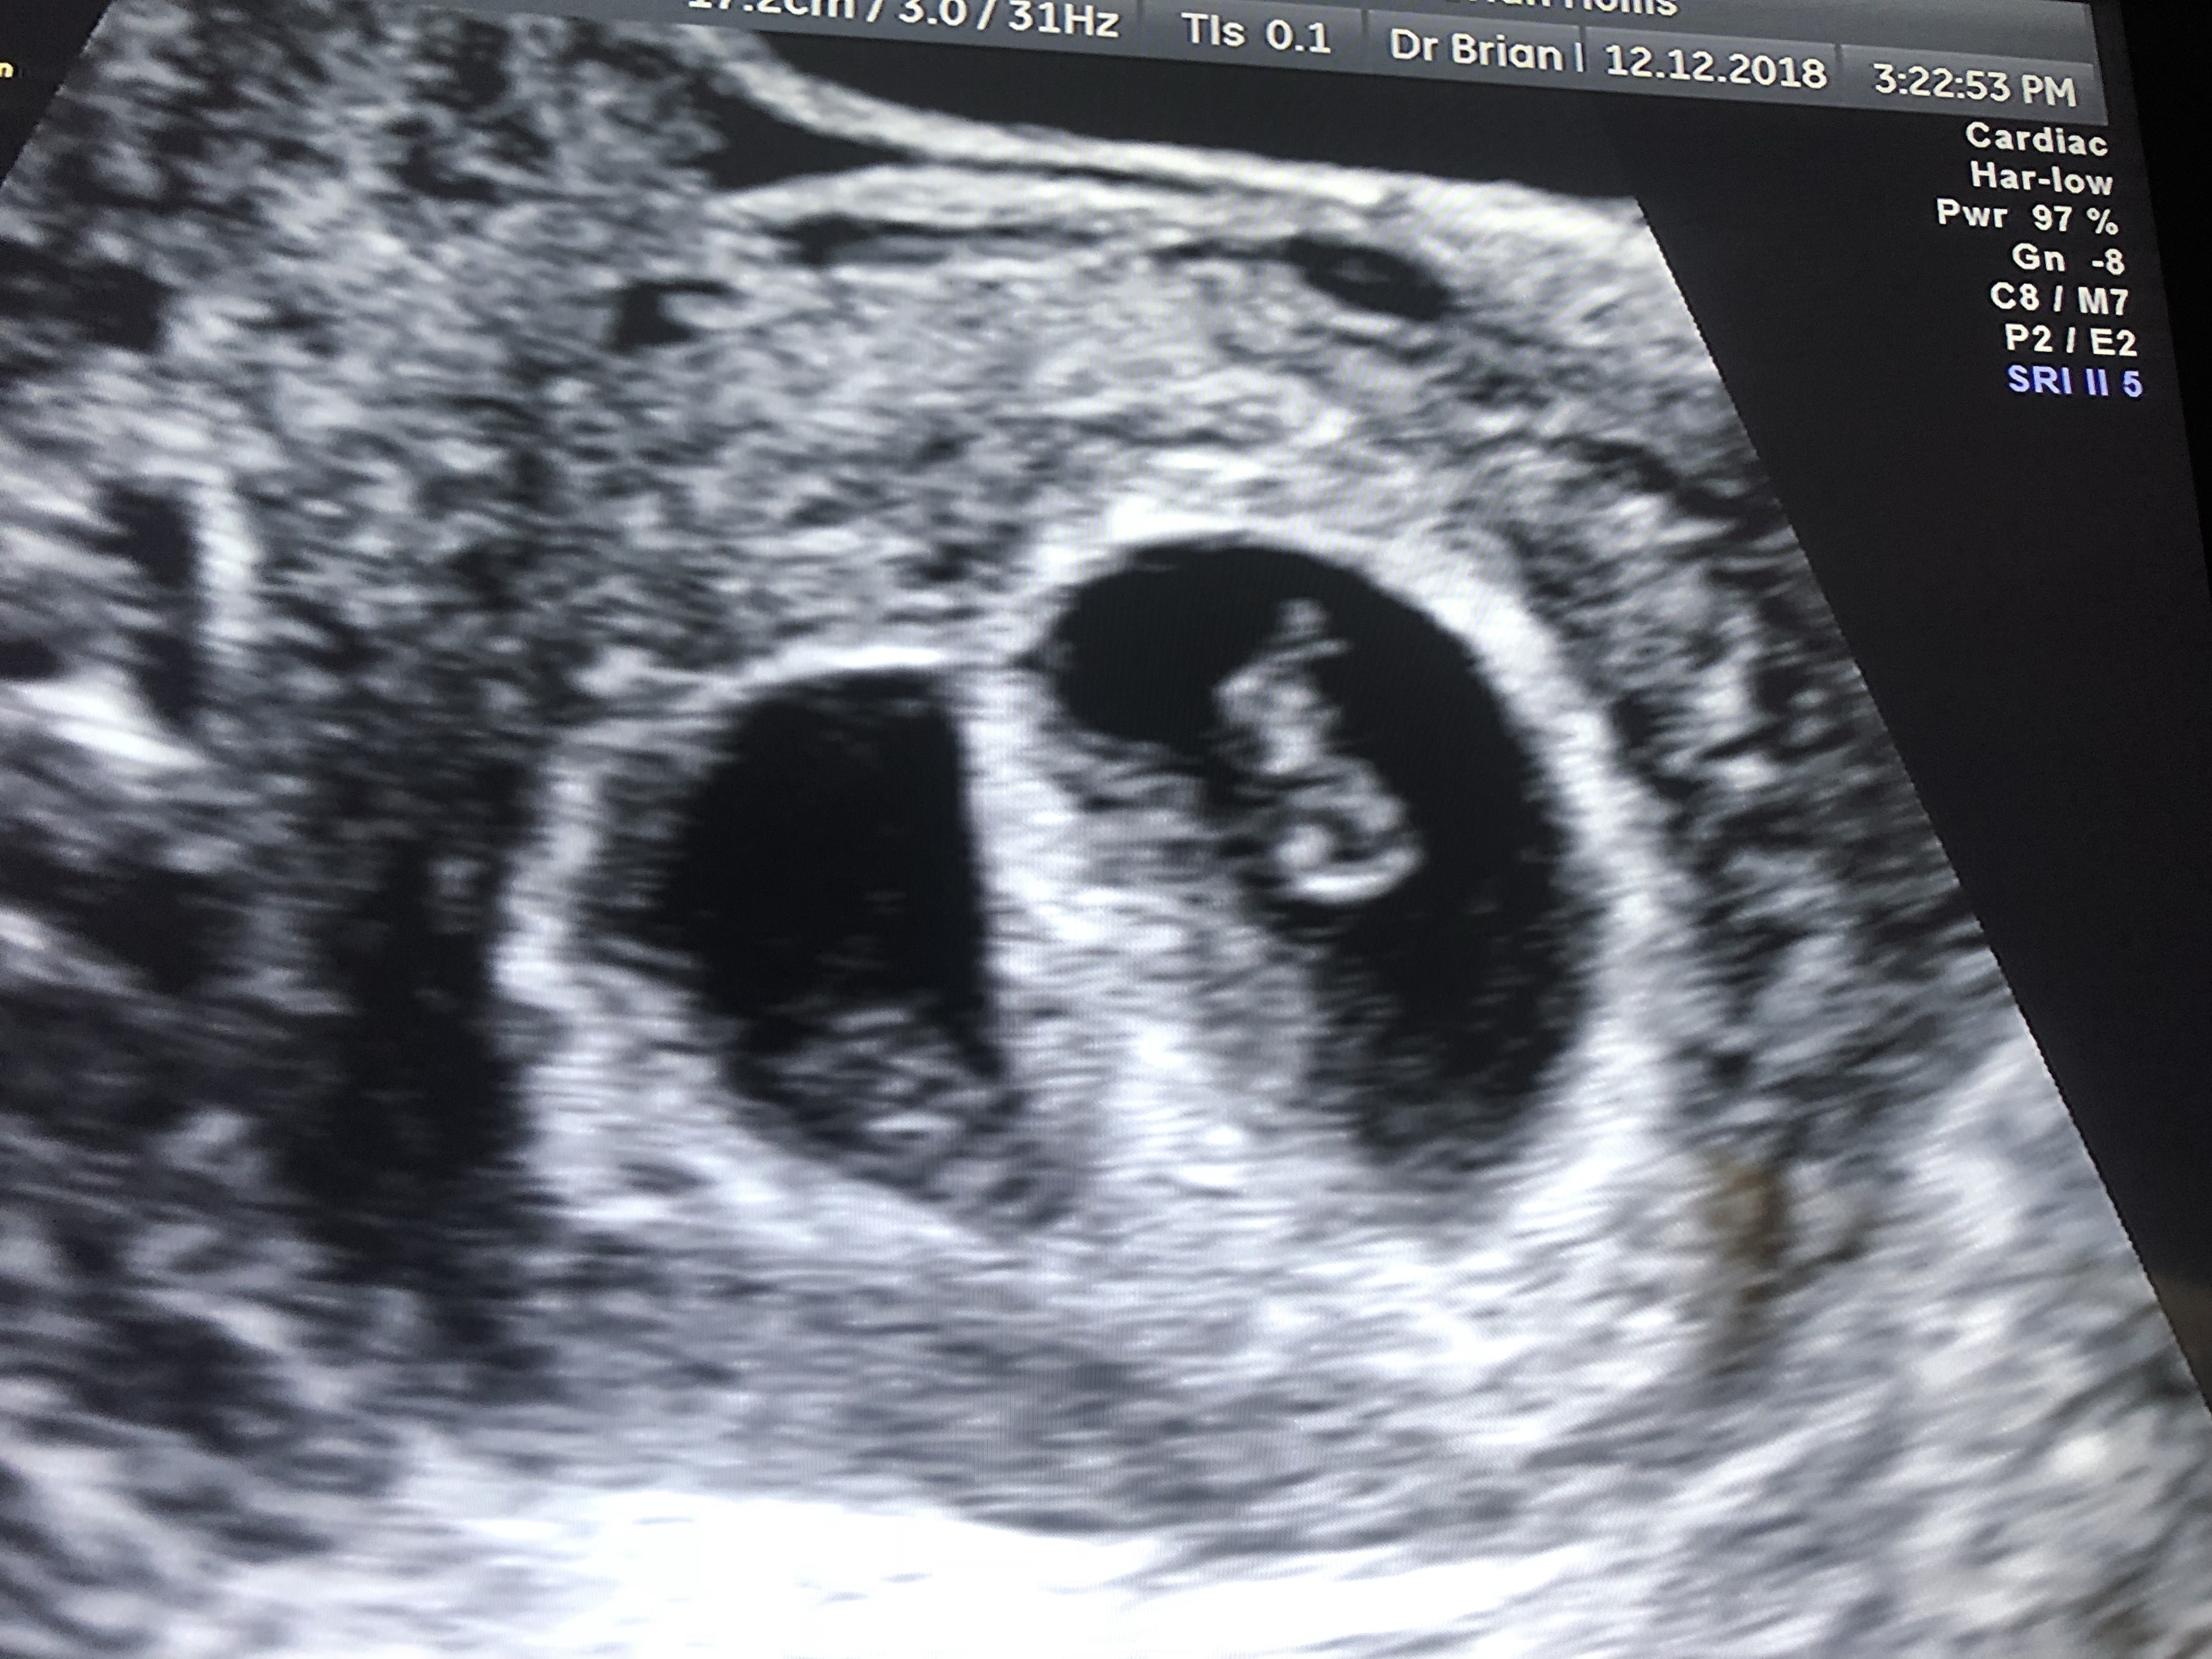

img_7533 Published November 18, 2019 at 4032 × 3024 in Exceedingly, abundantly and beyond Our two little flickers